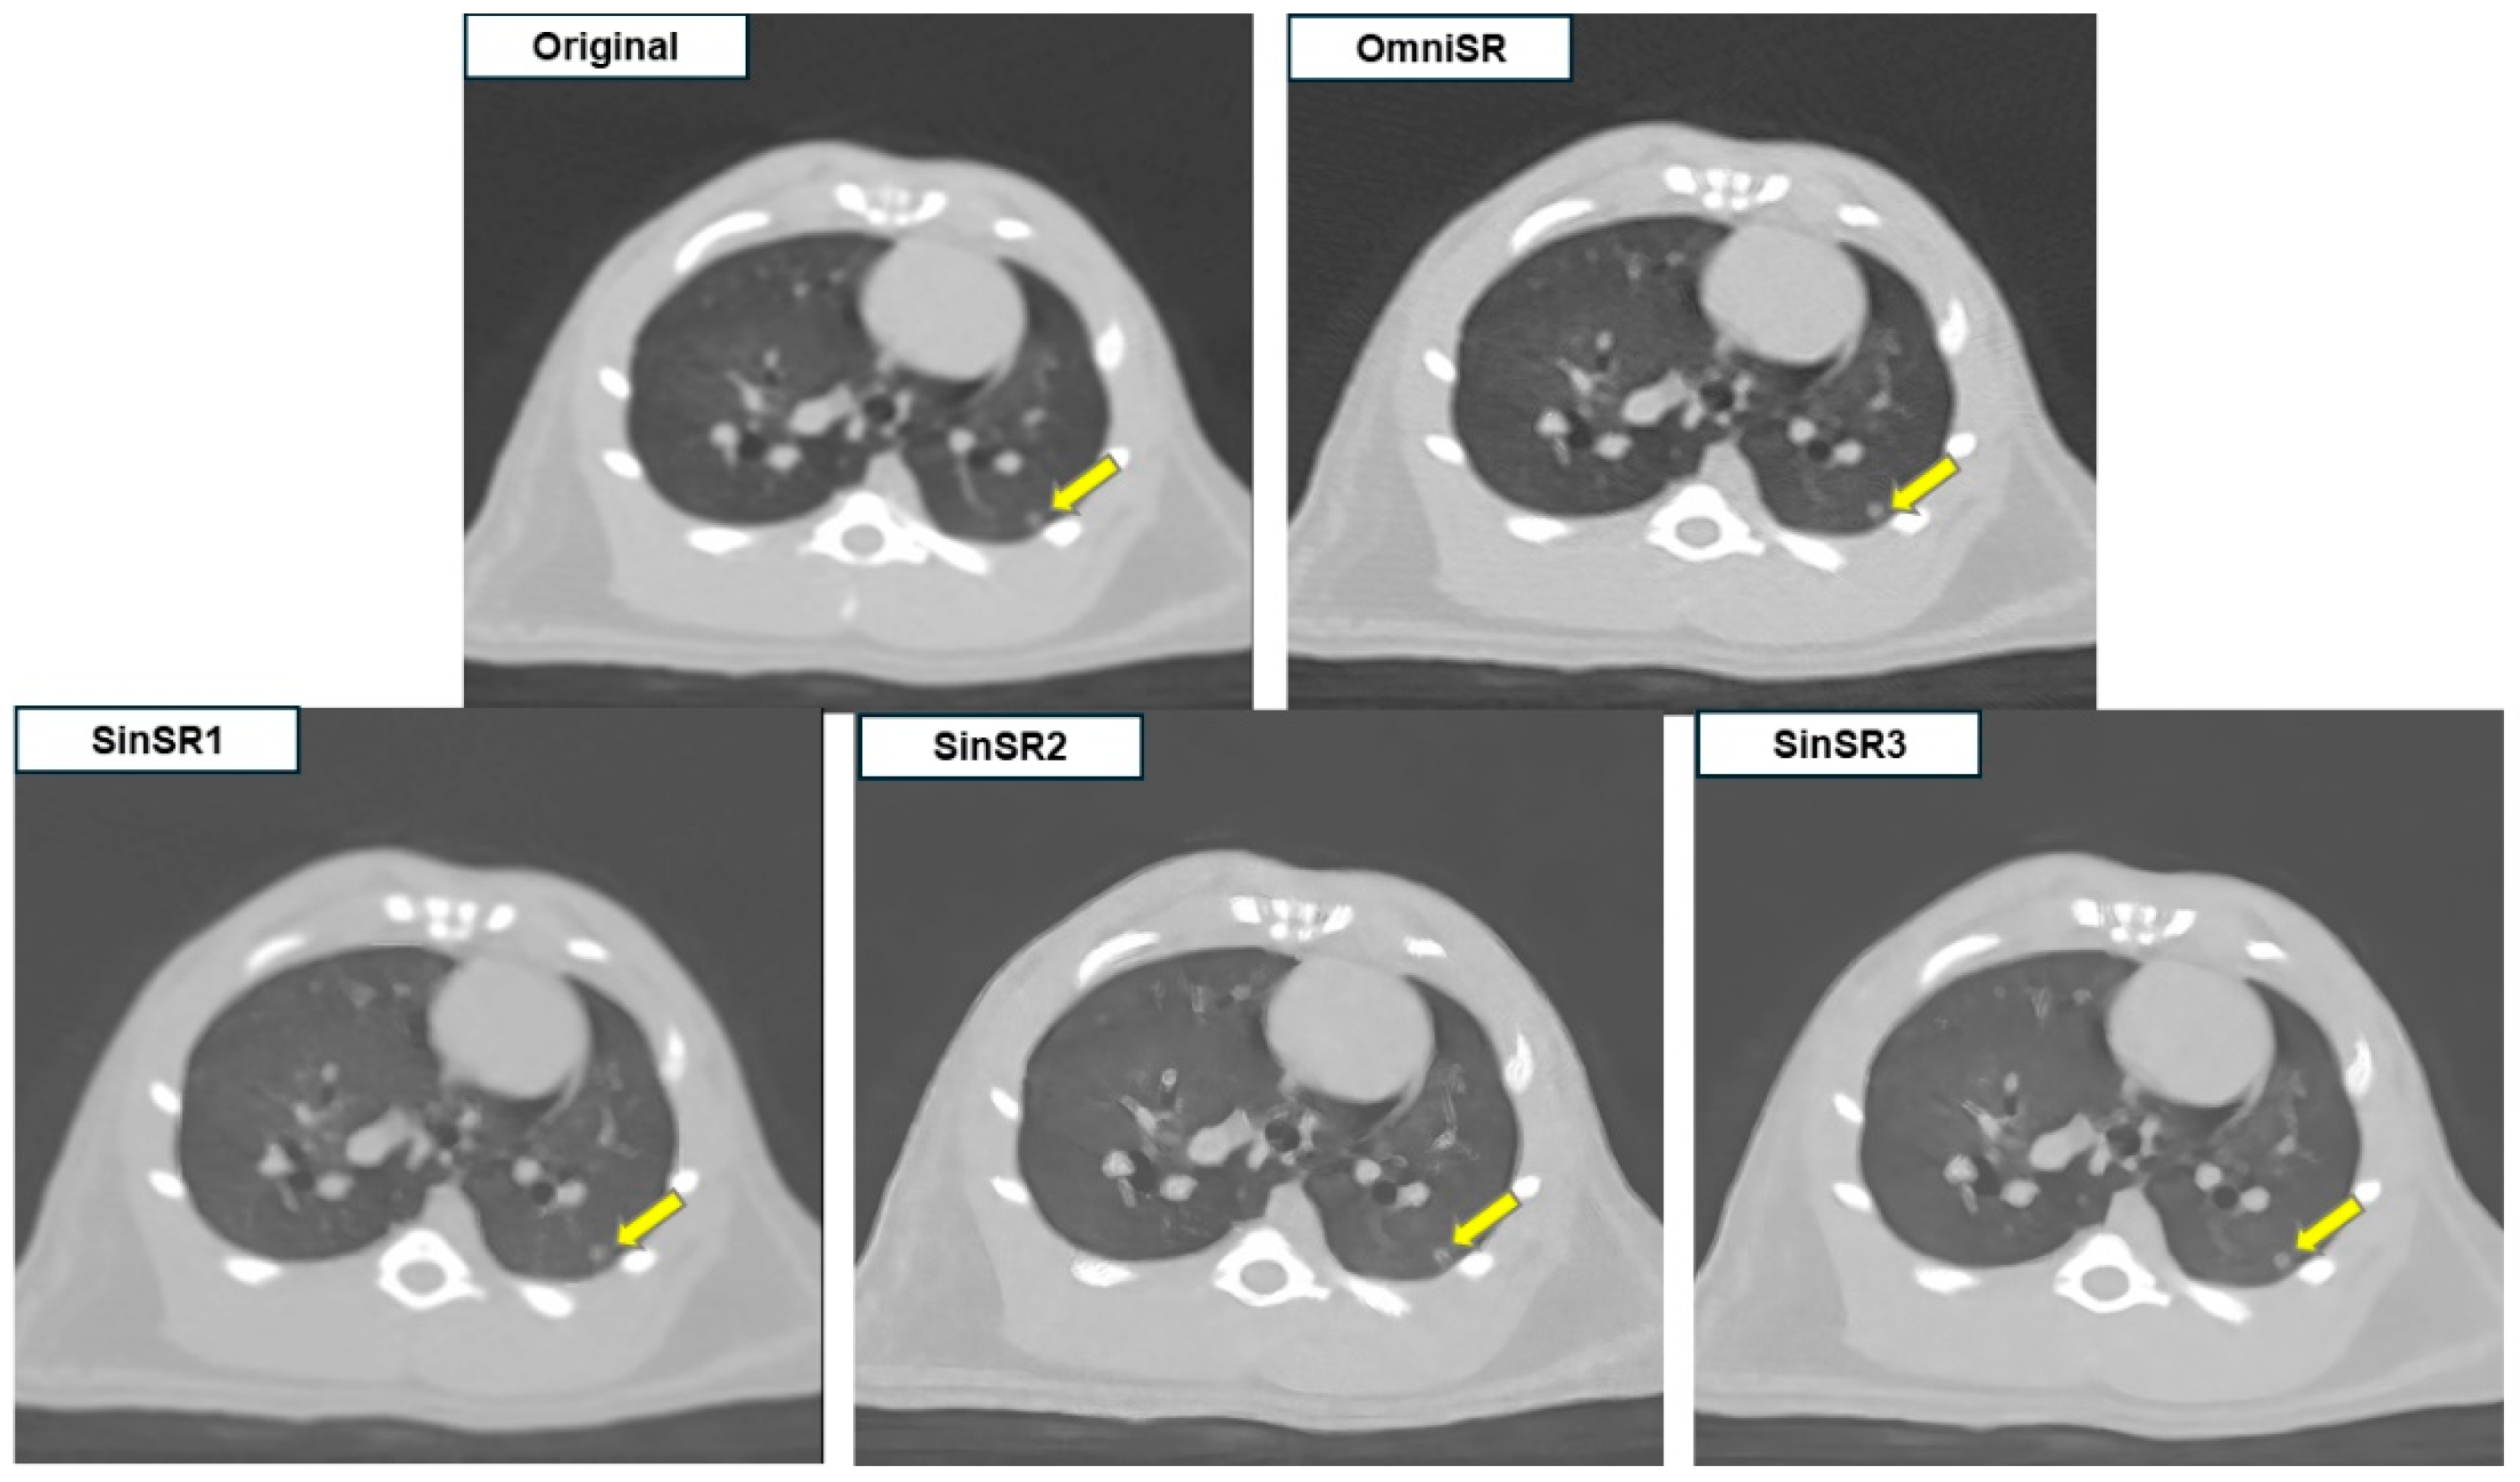

3.2. Subjective Image Analysis

| Margin of lesions | R1 | 4.07 ± 0.73 | 1.09 ± 0.32 | 1.10 ± 0.33 | 1.81 ± 0.90 | N/A |

| R2 | 3.88 ± 0.76 | 1.09 ± 0.32 | 1.10 ± 0.33 | 1.75 ± 0.82 | N/A | |

| Mean | 3.97 ± 0.75 | 1.09 ± 0.32 * | 1.10 ± 0.33 *† | 1.78 ± 0.86 *§ | <0.001 | |

| Nodule/mass detectability | R1 | 4.51 ± 0.85 | 1.25 ± 0.66 | 1.25 ± 0.66 | 1.50 ± 0.70 | N/A |

| R2 | 4.40 ± 0.83 | 1.15 ± 0.52 | 1.16 ± 0.53 | 1.67 ± 0.81 | N/A | |

| Mean | 4.46 ± 0.84 | 1.20 ± 0.59 * | 1.20 ± 0.60 *† | 1.58 ± 0.76 *§ | <0.001 | |